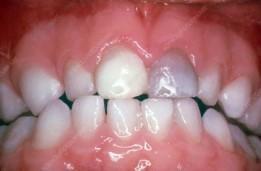

Tερηδόνες θηλασμού (nursing bottle caries)

Β/ ΤΡΑΥΜΑ(10)

Ο τραυματισμός των δοντιών και των ιστών που τα περιβάλλουν είναι πολύ συχνός στην παιδική ηλικία. Χρειάζεται έγκαιρη και σωστή αντιμετώπιση για περιορισμό μελλοντικών προβλημάτων.

α. Τραύμα στα νεογιλά δόντια

Όταν το τραύμα γίνει ενώ το παιδί έχει ακόμα παιδικά δόντια συνήθως γίνεται εμβύθιση στο κόκκαλο ή αποσπάται πλήρως από αυτό (εκγόμφωση).

Στην περίπτωση της εμβύθισης εξετάζουμε ακτινογραφικά αν έχει τραυματιστεί το οδοντικό σπέρμα του μόνιμου διαδόχου δοντιού.

Αν δεν έχει νεκρωθεί με το χρόνο επανέρχεται στην αρχική του θέση. Στην περίπτωση ολικής εκγόμφωσης παιδικού δοντιού δεν το βάζουμε πίσω στην θέση του, επικοινωνούμε με τον παιδοδοντίατρο για την εκτίμηση της κατάστασης.